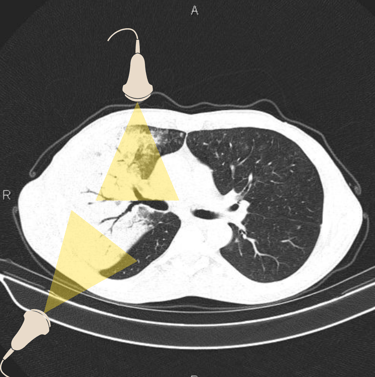

Figura 2. Veja como é possível diagnosticar essa extensa pneumonia utilizando os pontos do protocolo BLUE. Tomografia retirada de https://radiopaedia.org/cases/air-bronchogram-in-pneumonia#image-54184430, e editada pelo autor.

Essa pergunta pode ser respondida com o 7º princípio do US pulmonar, descrito por Lichtenstein: Distúrbios agudos possuem localização superficial e extensa (figura 2). Pensa comigo, nosso paciente está em insuficiência respiratória aguda, logo, o que quer que esteja causando uma apresentação clínica tão dramática, deve ser facilmente visível sem que o examinador precise "procurar demais".